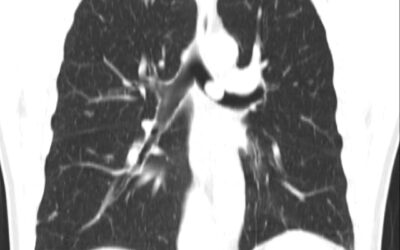

პაციენტი 24 წლის ქალბატონი. ტუბსაწინააღმდეგო ქიმიოთერაპიის დასრულებიდან რამოდენიმე თვეში გაუჩნდა ჩივილები: სპაზმური ხველა, ქოშინი, მსტვინავი სუნთქვა. გულმკერდის კტ კვლევით ინახა მარცხენა მთავარი ბრონქის ობტურაცია კარინის დონიდან სანათურის დიამეტრით 2მმ....